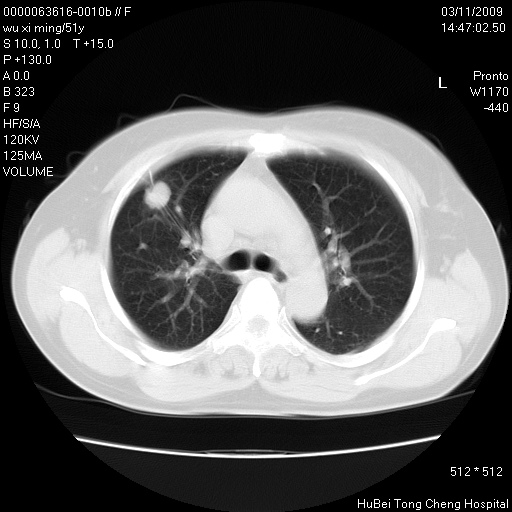

患者 女,51岁。因“胆囊炎,胆囊结石”,行常规术前胸部x线检查发现:右上肺结节病灶,建议行进一步检查。患者无咳嗽、咳痰及咯血等呼吸道症状,近期出现背部疼痛不适。

胸部ct轴位平扫(层厚10mm,螺距1.5,重建间隔10mm;部分层面:层厚3mm,螺距1.0,重建间隔3mm),图像如下:

1、周围型肺癌。(毛刺正、血管束集征,分叶。)

集束征,胸膜牽拉征,毛刺,淺分葉高度提示ca.

右肺周围型肺癌伴肺内转移及胸椎转移。已无手术机会。